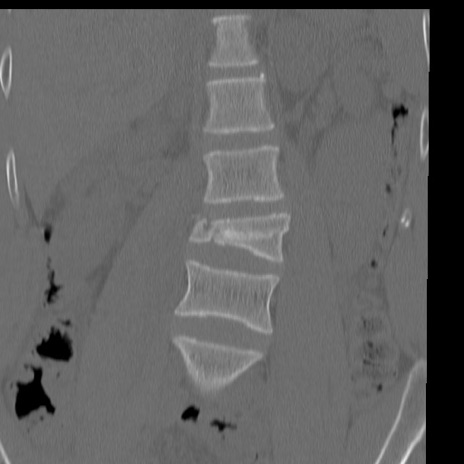

症例3 腰椎CT(冠状断像)

【症例】30歳代男性

【主訴】腰痛

【現病歴】本日旅行先で観光中に、友人と衝突し転倒し受傷。

【身体所見】麻痺なし、右下腿内側前面外側、左下腿内側に知覚鈍麻・しびれ

腰椎CT

矢状断像